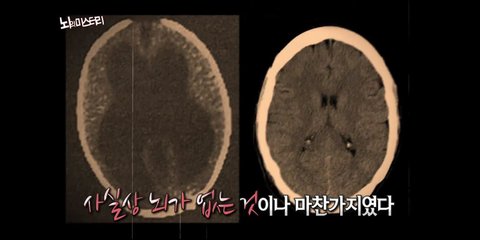

어제 위라보니까 응....